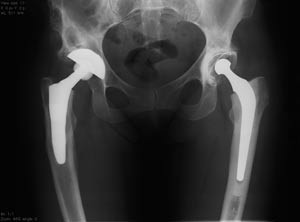

For 25 år siden – i 1980 – hadde ortopedifaget vært gjennom en rivende utvikling og stod sterkt i Norge. De nye frakturbehandlingsteknikkene hadde ført ortopedene fra gips og immobilisering til AO-prinsippene om funksjonell kirurgisk bruddbehandling. Liggetiden for mange brudd gikk radikalt ned, og stadig flere bruddtyper ble behandlet kirurgisk. Norske ortopeder var med i utviklingen av nye implantater. Mens noen arbeidet med nye platetyper, var andre opptatt med ekstern fiksasjon og margnagler, som etter hvert revolusjonerte bruddbehandlingen. Gruppene ved Haukeland Sykehus, Ullevål sykehus og i Trondheim utviklet sammen med industrien nye implantater til bruk på brudd i øvre femurende. Det tradisjonelle frakturbehandlingskurset på Voss fikk en sentral stilling i nyutviklingen og utdanningen av alle norske kirurger. Samtidig hadde protesekirurgien, først i hofteledd, senere i kne, skulder og albueledd gjort sitt inntog. Plutselig kunne man med gode kirurgiske teknikker gi pasienter med hofteslitasje et nytt liv. Mens frakturbehandlingsutviklingen ble ledet av de akuttorienterte sykehusene, var det Sophies Minde, Martina Hansens Hospital, Kysthospitalet i Hagavik og Sentralsykehuset i Rogaland som ledet an utviklingen innenfor protesekirurgien. Charnleys «low friction» sementerte hofteprotese fikk innpass. Dette åpnet opp for en utvikling de neste 25 år med sementerte og usementerte proteser i hofte og kneledd, senere fulgt av proteser i skulder og albue og til sist i ankelledd.

Samtidig med en rivende faglig utvikling frem til 1980 startet også spesialitetsutviklingen. Faget vokste og ble stort. Det ble tidlig klart at generelle kirurger ikke kunne beherske alle de nye ortopediske teknikkene. De kirurgiske avdelingene ble splittet, og egne ortopediske avdelinger vokste frem. I dag har alle de større sykehusene egne ortopediske avdelinger. Typisk er det at det tradisjonelle bruddbehandlingskurset på Voss er utvidet med et avansert kurs der alle de nye teknikkene diskuteres. Moderne traumebehandling betyr rask kirurgi, men ofte ikke endelig kirurgi. Det betyr utstrakt bruk av midlertidig ekstern fiksasjon på ekstremiteten, men også en økning av kirurgi med store implantater på rygg og i bekken-acetabulum. Størst utvikling de siste 25 år har det trolig vært innenfor kikkhullskirurgien. I dag gjøres en stor del av leddkirurgien i skulder, albue, håndledd, hofte, kne og ankelledd artroskopisk. Dette har ført til en sterk økning i dagkirurgi og raskere tilbakeføring til arbeid for pasienten. Proteseutviklingen har fortsatt, om enn ikke i samme tempo som i slutten av 1980-årene og begynnelsen av 90-årene. Gjennom opprettelsen av Nasjonalt proteseregister i Bergen har norske ortopeder fått et instrument for kvalitetssikring på dette feltet som mange misunner oss. Registeret viser den store økningen som har skjedd i kneprotesekirurgi og en endringstendens fra sementert til usementerte proteser. Forskningsmessig har kanskje det mest spennende miljøet ligget i Trondheim, med utvikling av den skreddersydde hofteprotese for spesielle pasienter. Ryggkirurgien har fått mye oppmerksomhet i mediene, mest på grunn av lange ventelister og økt etterspørsel fra pasientene. Mens kirurgisk behandling av medfødte og ervervede misdannelser (f.eks. skolioser) har utviklet seg teknisk, har kravet om mer kirurgi ved degenerative lidelser ikke ført til gjenombrudd. Kirurgisk behandling på dette feltet er fortsatt kontroversielt – heldigvis drives det nå mye forskning i Norge på området. Den tekniske utviklingen – med nye implantater, stadig mindre snitt og mer funksjonell behandling har preget alle de andre områdene innen ortopedien i den grad at stadig nye subspesialiteter kommer til. Det er blitt umulig for en ortoped å beherske alle områdene med alle de nye teknikkene.